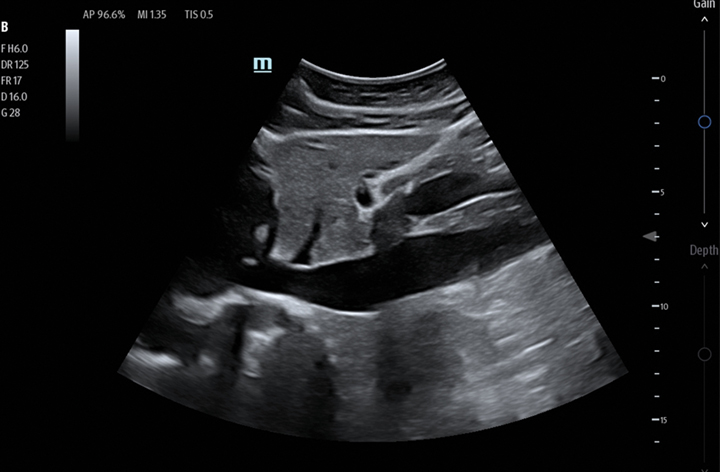

The TE7 Max Ultrasound System is designed to maximize your capabilities in demanding Point of Care environments. With its thoughtful industrial design and best-in-class image quality, the

TE7 Max provides a superior user experience during rapid clinical assessments and procedures taking place at the patient’s bedside

or on the go.

The TE7 Max boasts a large 21.5” vertically oriented high-definition display and a sealed touch-based interface to optimize visualization and accessibility when every second counts. The TE7 Max also incorporates a comprehensive suite of artificial intelligence (AI) powered Smart Tools and workflow enhancement software (iWorks™ Protocol) making efficiency and reproducibility the expectation for all end users.